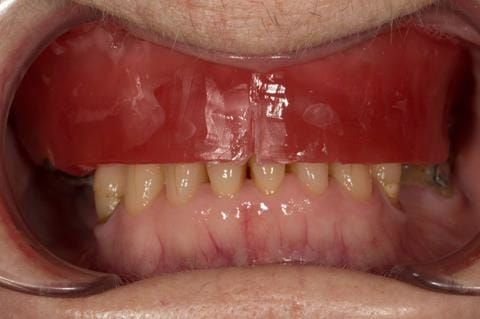

- Cobalt chromium reinforced gasket denture - using a Molloplast B "O" ring to retain and stabilise the denture. This was my professional preference as this was the least invasive and simplest solution to this dental problem. Should the UR7 require removal in the future - an artificial tooth could be added - resulting in a complete denture. The patient would have adapted to the denture fully by this stage and have good neuromuscular control of the prosthesis.

Following consultation and second discussion appointment the patient chose to have option 2 namely, a window denture - maxillary cobalt chromium based partial denture. The clinical situation and treatment process is shown in detail below with photographs. The patient was successfully rehabilitated with this and her quality of life considerably improved. The clinical work was provided by Finlay and the technical work by Rowan.